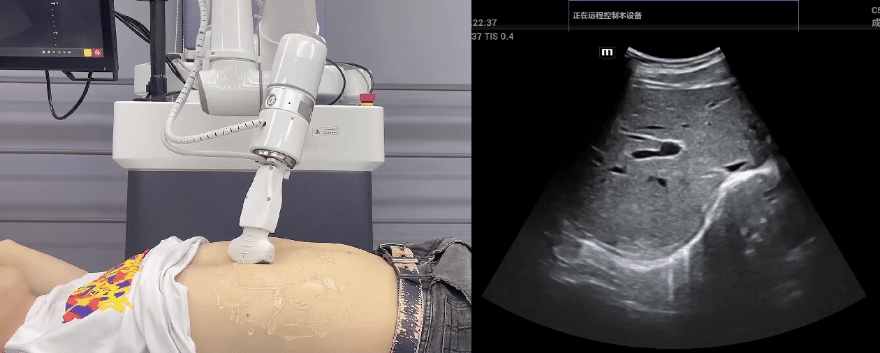

今年会jinnianhui(中国)协作机器人搭载库柏特自主研发的机器人遥操作、多模态数据采集与处理、机器人模仿学习、机器人力位控制等技术升级变革传统超声,可实现远程+自主超声扫查与诊断,从传统远程超声仅能对话会诊变革升级为能对话、能操作,使得基层患者可就近享受异地三甲专家扫诊服务。实现专家端与患者端远程连接,并支持专家端与多路患者端自由切换控制。

今年会jinnianhui(中国)机器人末端搭载超生L13-3N线阵探头,可以对浅表小器官和外周血管进行超声检查;搭建C5-1s凸阵探头,可以对腹部(肝、胆、胰、肾等器官进行超声检查)

今年会jinnianhui(中国)协作机器人优秀的主从位姿控制、主从接触力控制、零力拖拽功能,为采集与复原专业医生的检测位置、姿态和压力手法提供了极大便利。

EC66协作机器人末端可搭载主流品牌高品质超声仪,让操作指令和影像低延迟、高精准、高保真传输,确保检查可靠、医患放心;智能力控等三重防护系统,确保患者舒适、安全。

今年会jinnianhui(中国)协作机器人与超声深度打通,最大程度保留医生左右手同时操作传统超声的习惯,并改善其舒适性,超声检查实际应用场景展示如下: